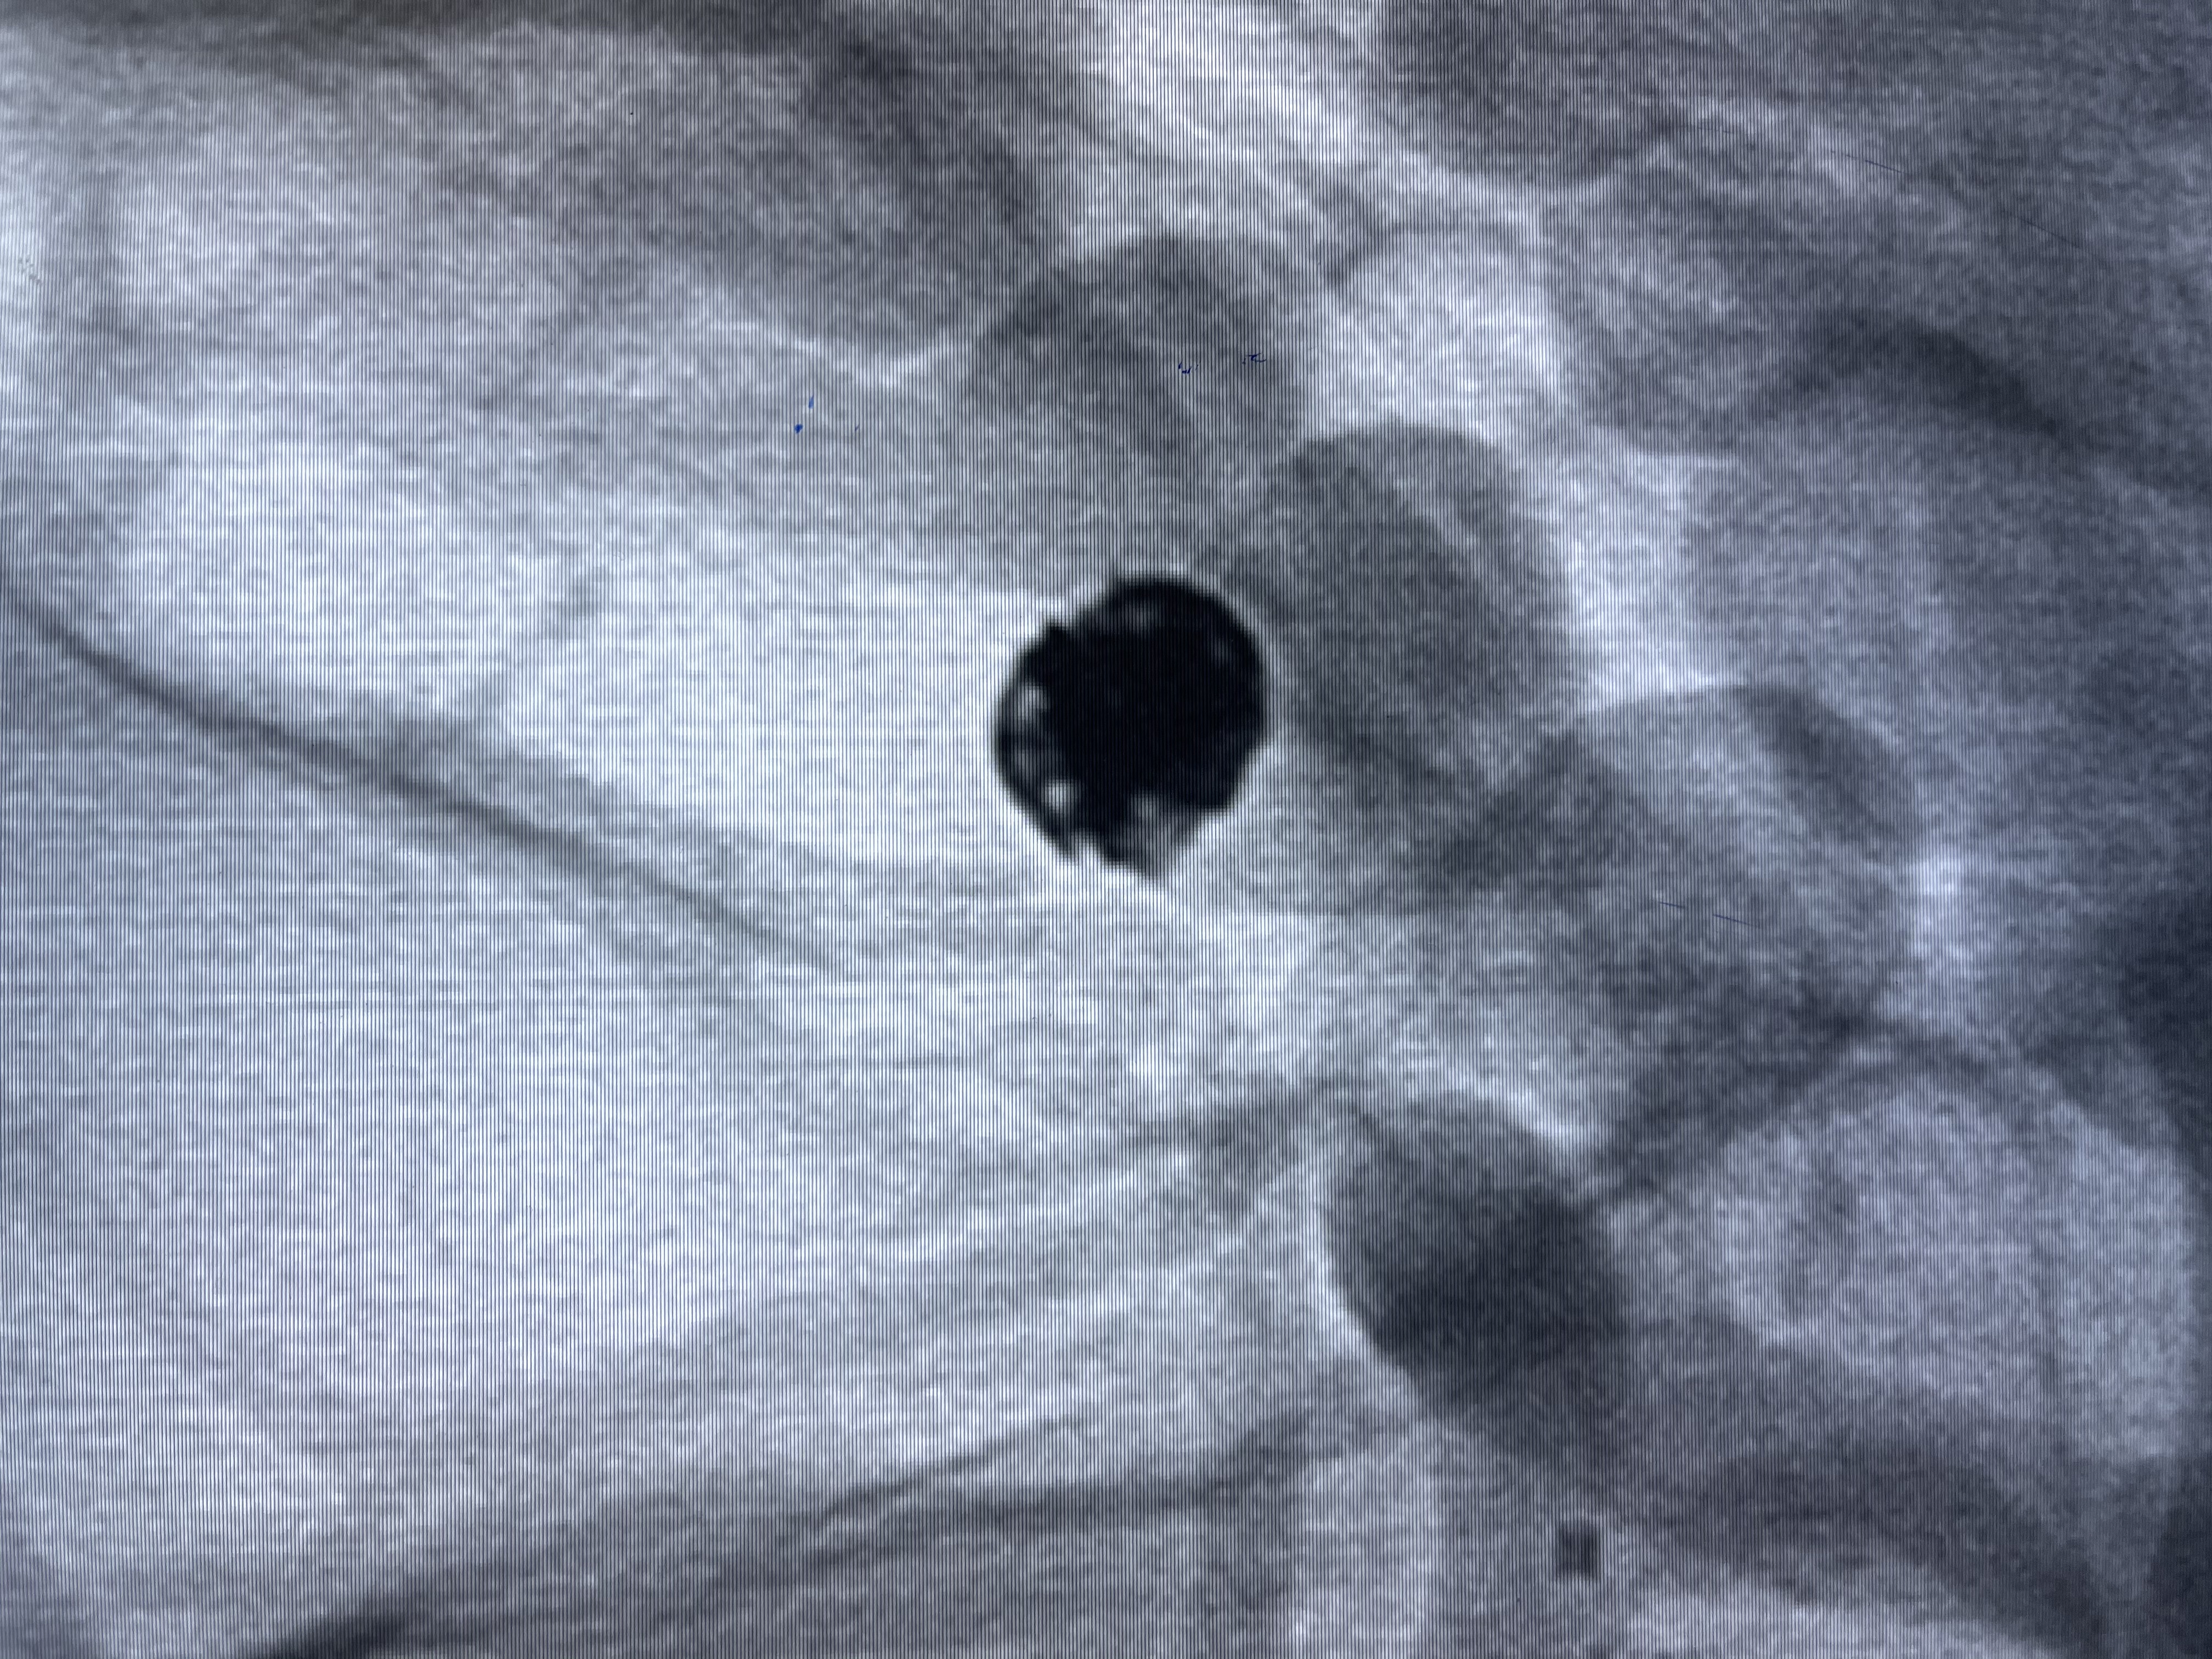

动脉瘤致密填塞

麻醉苏醒佳

术后即刻CT